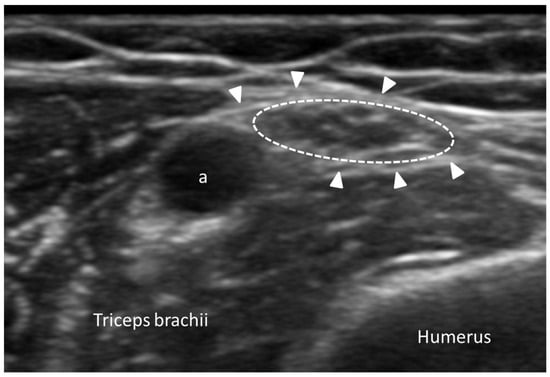

3.5.3. Myofascial Trigger Points